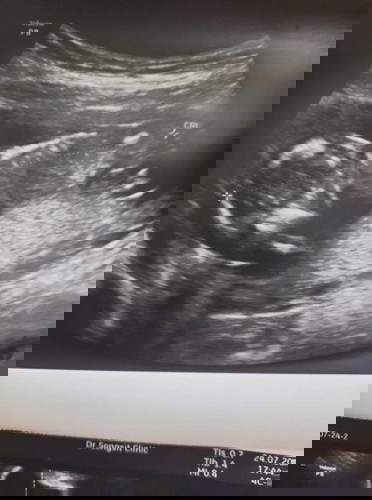

สอบถามหน่อยค่ะ รูปลูกของหนูอยู่ในท่าปกติใช่ไหมค่ะ กังวลมากค่ะ ประมาณ 14w กว่าๆ ตอบหน่อยนะค่ะ

น้องอยู่ได้ทุกท่าค่ะแม่ ไม่ต้องกังวลน้า